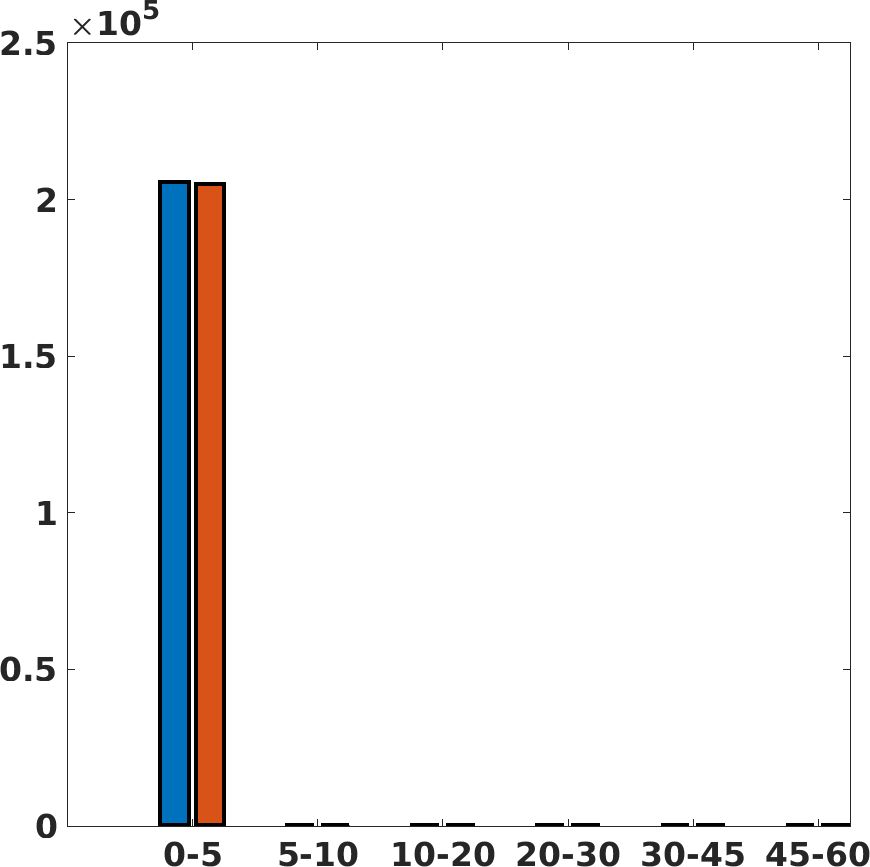

Fig. 7(a-b-c, left) shows the box plot of the statistics of the PSNR on three different anatomical districts, comparing the target images with the prediction and the cubic convolution, respectively. The metrics are computed on a data set of 200 images of the same district and with the same up-sampling factor. We report that the PSNR median value improves of on obstetric 2X raw images, on cardiac 2X raw images, and on abdominal raw 4X images.

Fig. 7(a-b-c, right) shows the histogram of the absolute value of the error with respect to the target image, of the prediction and Cubic convolution results, respectively. The histograms show the number of pixels where the prediction error is lower than 5 (i.e., the first bin of the histogram), which means very similar to the target when visually analysing the images. From the Cubic convolution to the predicted images, this value increases of on obstetric 4X raw images, on cardiac 4X raw images, and on abdominal 4X raw images.

Fig. 17 (left) shows the box plot of the quantitative metrics, comparing the target images with the prediction and the Cubic convolution, respectively. The PSNR metric is computed on a data set of 200 images, belonging to the same district, and with the same up-sampling factor. Analysing the obstetric anatomical district and concerning the corresponding raw images (Fig. 7 (a, left)), the denoising allows the network to significantly improve the results of the up-sampling and the prediction. In particular, comparing the target images with the predicted images, the median PSNR value of obstetric 2X denoised images is 51.8, compared to the median PSNR value of obstetric 2X raw images which is 36.9.

Fig. 17 (right) shows the histogram of the absolute value of the error with respect to the target, of the prediction and Cubic convolution respectively. This result shows that our framework increase of and (2X and 4X, respectively) the number of pixels where the prediction error is lower than 5, which is very similar to the target when visually analysing the images, and improved with respect to the learning framework applied to raw images. According to Fig. 18, our method improves the accuracy of Cubic convolution. For example, the SSIM increases of on cardiac 2X and the MAE increases of on abdominal 4X.